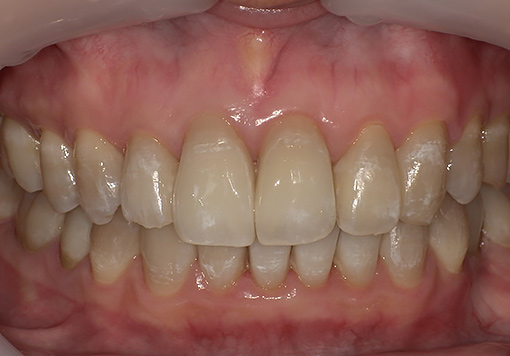

Case 01

before

after

- 主訴:歯並びが気になる

- 治療内容:下顎のみマウスピース矯正

- 治療期間:1年間6ヶ月

- 診断結果:歯列不正

- 治療後経過:経過良好

- 治療費用:40万円

リスク・副作用:歯肉退縮、歯の動揺、歯根吸収